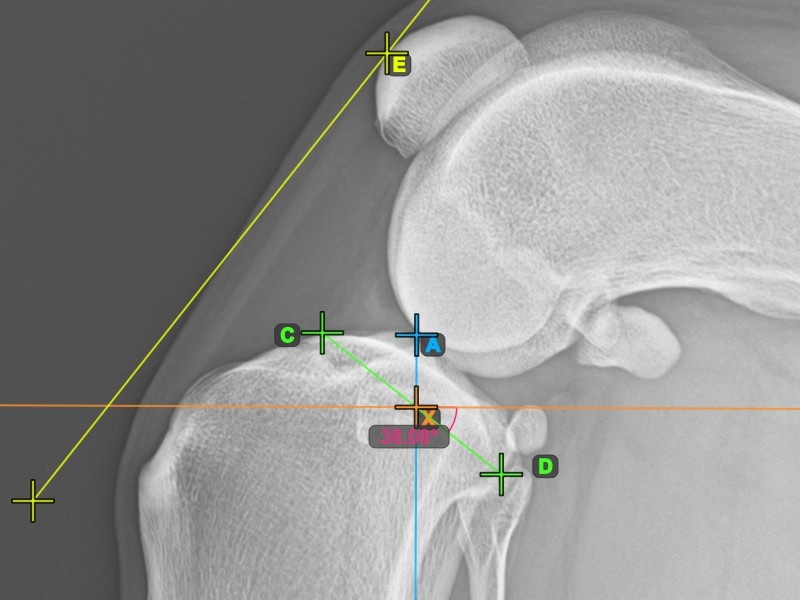

Starten Sie das TTA-Messverfahren, indem Sie den vordersten Punkt der Patella markieren.

Das Bild unten zeigt die übliche Platzierung des vordersten Punkts der Patella.

Um das TTA-Messverfahren abzuschließen, markieren Sie den hintersten Punkt der Crista Tibiae (Tuberositas Tibiae). Der Abstand zwischen der Tuberositas Tibiae und der Linie, die durch den vordersten Punkt der Patella verläuft, ist die erforderliche Anpassung für das TTA-Verfahren.

Das Bild unten zeigt die übliche Platzierung der Tibiatuberositas, des markantesten Punkts des Tibiakamms.